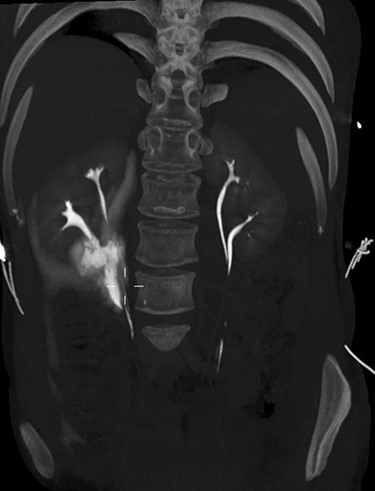

3D maximum intensity projection image of bilateral duplex kidneys and the contrast extravasation from the inferior moiety.